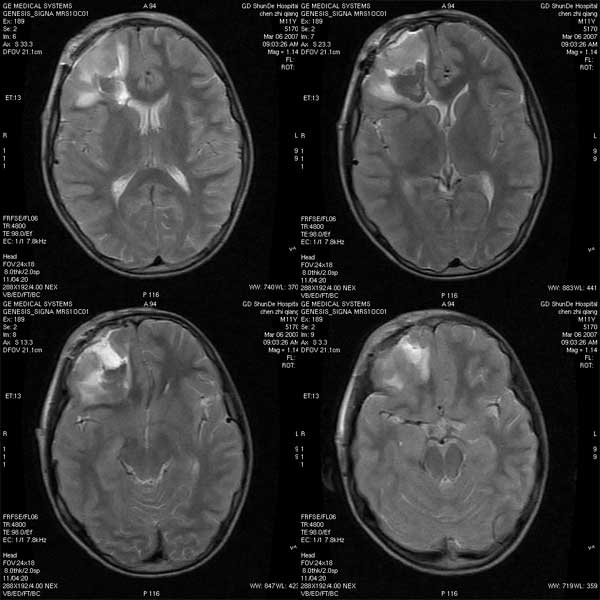

性别:m

年龄:11

病历摘要:右颞开放性颅脑损伤治疗后复查